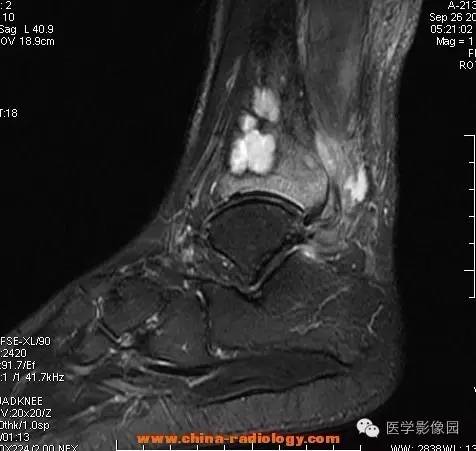

影像学表现:胫骨中下段干骺端不未规则形长T1长T2信号,T2WI见不完整环形稍低信号影,T2脂肪抑制低信号更明显,并见胫骨下段及踝关节后外侧软组织呈弥漫稍高信号,增强明显不均匀强化,增强见低信号环内有环形强化影。

影像学表现:表现为长骨干骺端有椭圆形密度减低区,边缘有清晰的骨质硬化,病变与邻近正常骨髓腔境界清楚。MRI上T1WI呈低信号,少数呈等信号,T2WI多为混杂高信号,增强扫描可见环状强化,强化的脓肿壁薄而均匀。